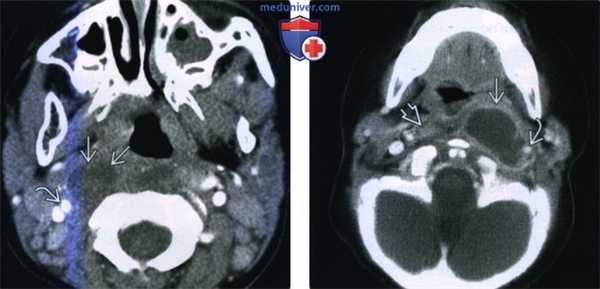

(Слева) При КТ с КУ в аксиальной проекции визуализируется левосторонний МА и ПТА, распространяющийся через капсулу миндалины в заднее щечное пространство и медиальную крыловидную мышцу жевательного пространства. Отмечается накопление контраста в правой воспаленной миндалине, но данных за абсцедирование здесь нет.

(Справа) При КТ с КУ в аксиальной проекции наблюдается осложненный левосторонний МА больших размеров. Инфекционный процесс распространился в сонное пространство В, в переднелатеральном направлении в верхнее поднижнечелюстное пространство, в латеральном направлении в нижние отделы пространства околоушной железы.

2. КТ при нагноении заглоточных лимфоузлов:

• КТ без контрастирования:

о Увеличение размеров предпозвоночных мягких тканей

о Визуализация отдельного лимфоузла затруднена

• КТ с КУ:

о Увеличенный узел низкой плотности

о Возможно накопление контраста по периферии лимфоузла

о Целлюлит ЗГП ± сужение внутренней сонной артерии:

- Вазоспазм чаще встречается у детей, обычно разрешается самостоятельно

(Слева) КТ с КУ, аксиальная проекция. Правая внутренняя сонная артерия смещена латерально неоднородным образованием округлой формы. Отмечается увеличение одного из заглоточных лимфоузлов, а его сниженная плотность свидетельствует о раннем нагноении.

(Справа) КТ с КУ, аксиальная проекция. Крупный нагноившийся лимфоузел в заглоточном пространстве (ЗГП). Жидкостное образование с кольцом накопления контраста окружает внутреннюю сонную артерию, суженную из-за спазма, который может пугающе выглядеть на снимках, но в большинстве случаев разрешается самостоятельно. Обратите внимание на реактивную лимфаденопатию в правом отделе заглоточного пространства.